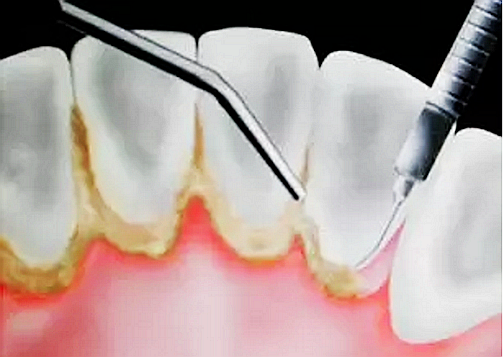

牙結(jié)石首先在牙齒與牙齦的交界處沉積,如果堆積的牙結(jié)石沒有及時去除,面積會越來越大,并朝著牙齦下發(fā)展,導(dǎo)致牙齦炎癥。牙齦炎癥會引起牙齦腫痛,這種腫痛感就像皮膚被針刺一樣。

由于不使用牙線、刷牙方式的不正確,或者其他因素(如牙列不齊、口腔內(nèi)有不良修復(fù)體、藥物作用、激素水平的變化)的影響,也許一個人只有牙齦上的結(jié)石,沒有牙槽骨吸收的現(xiàn)象,此時只需常規(guī)的潔牙。

當(dāng)牙齦下存在的牙結(jié)石,或有牙槽骨吸收跡象時,常規(guī)潔牙往往無法清除牙齦下的結(jié)石,此時需要進(jìn)行牙周刮治了。